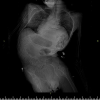

Samsun'da bir hastanın omurga eğriliği 5,5 saatlik ameliyatla düzeltildi

Samsun'da, skolyoz (omurga eğriliği) nedeniyle nefes almakta zorluk çeken ve kaburgaları kırılmaya başlayan serebral palsi hastası Enes Serçe, ameliyatla sağlığına kavuştu.

Enes Serçe'nin omurgasındaki eğrilik hastanede 5,5 saat süren ameliyatla giderildi.

Hastanın, omurga eğriliğinde artma, solunum kapasitesinde azalma, iç organ baskılarının artması ve kaburgalarının kırılmaya başlaması nedeniyle ameliyat edildiğini anlatan Bozduman, "Hastamızı yaklaşık 5,5 saatlik ameliyatla başarıyla tedavi ettik. Yedi gündür hastamızı takip ediyorduk, artık taburcu edilebilir duruma geldi." dedi.